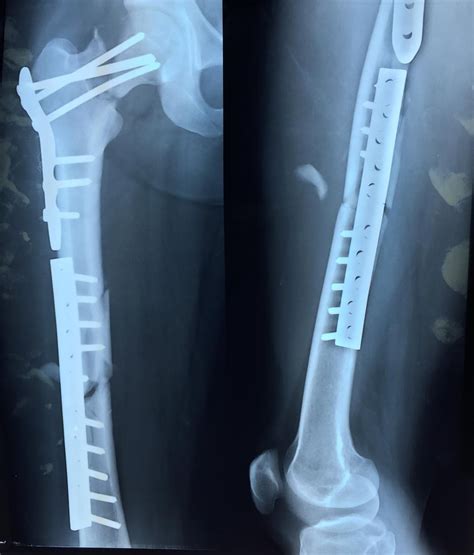

Fractures of the Neck of Femur

Fractures of the neck of femur are common, particularly in older adults and individuals with osteoporosis. These fractures can be classified into several types based on their location and pattern:

• Subcapital Fractures: Occur just below the femoral head.

• Transcervical Fractures: Occur in the middle of the femoral neck.

• Basicervical Fractures: Occur at the base of the femoral neck, near the junction with the femoral shaft.

Fractures of the neck of femur often result from falls or high-impact trauma. They can be particularly challenging to treat due to the limited blood supply to the femoral head, which can lead to complications such as avascular necrosis.

Surgical interventions may be necessary in more severe cases, such as:

• Open Reduction and Internal Fixation (ORIF): To realign and stabilize the bone using plates, screws, or rods.